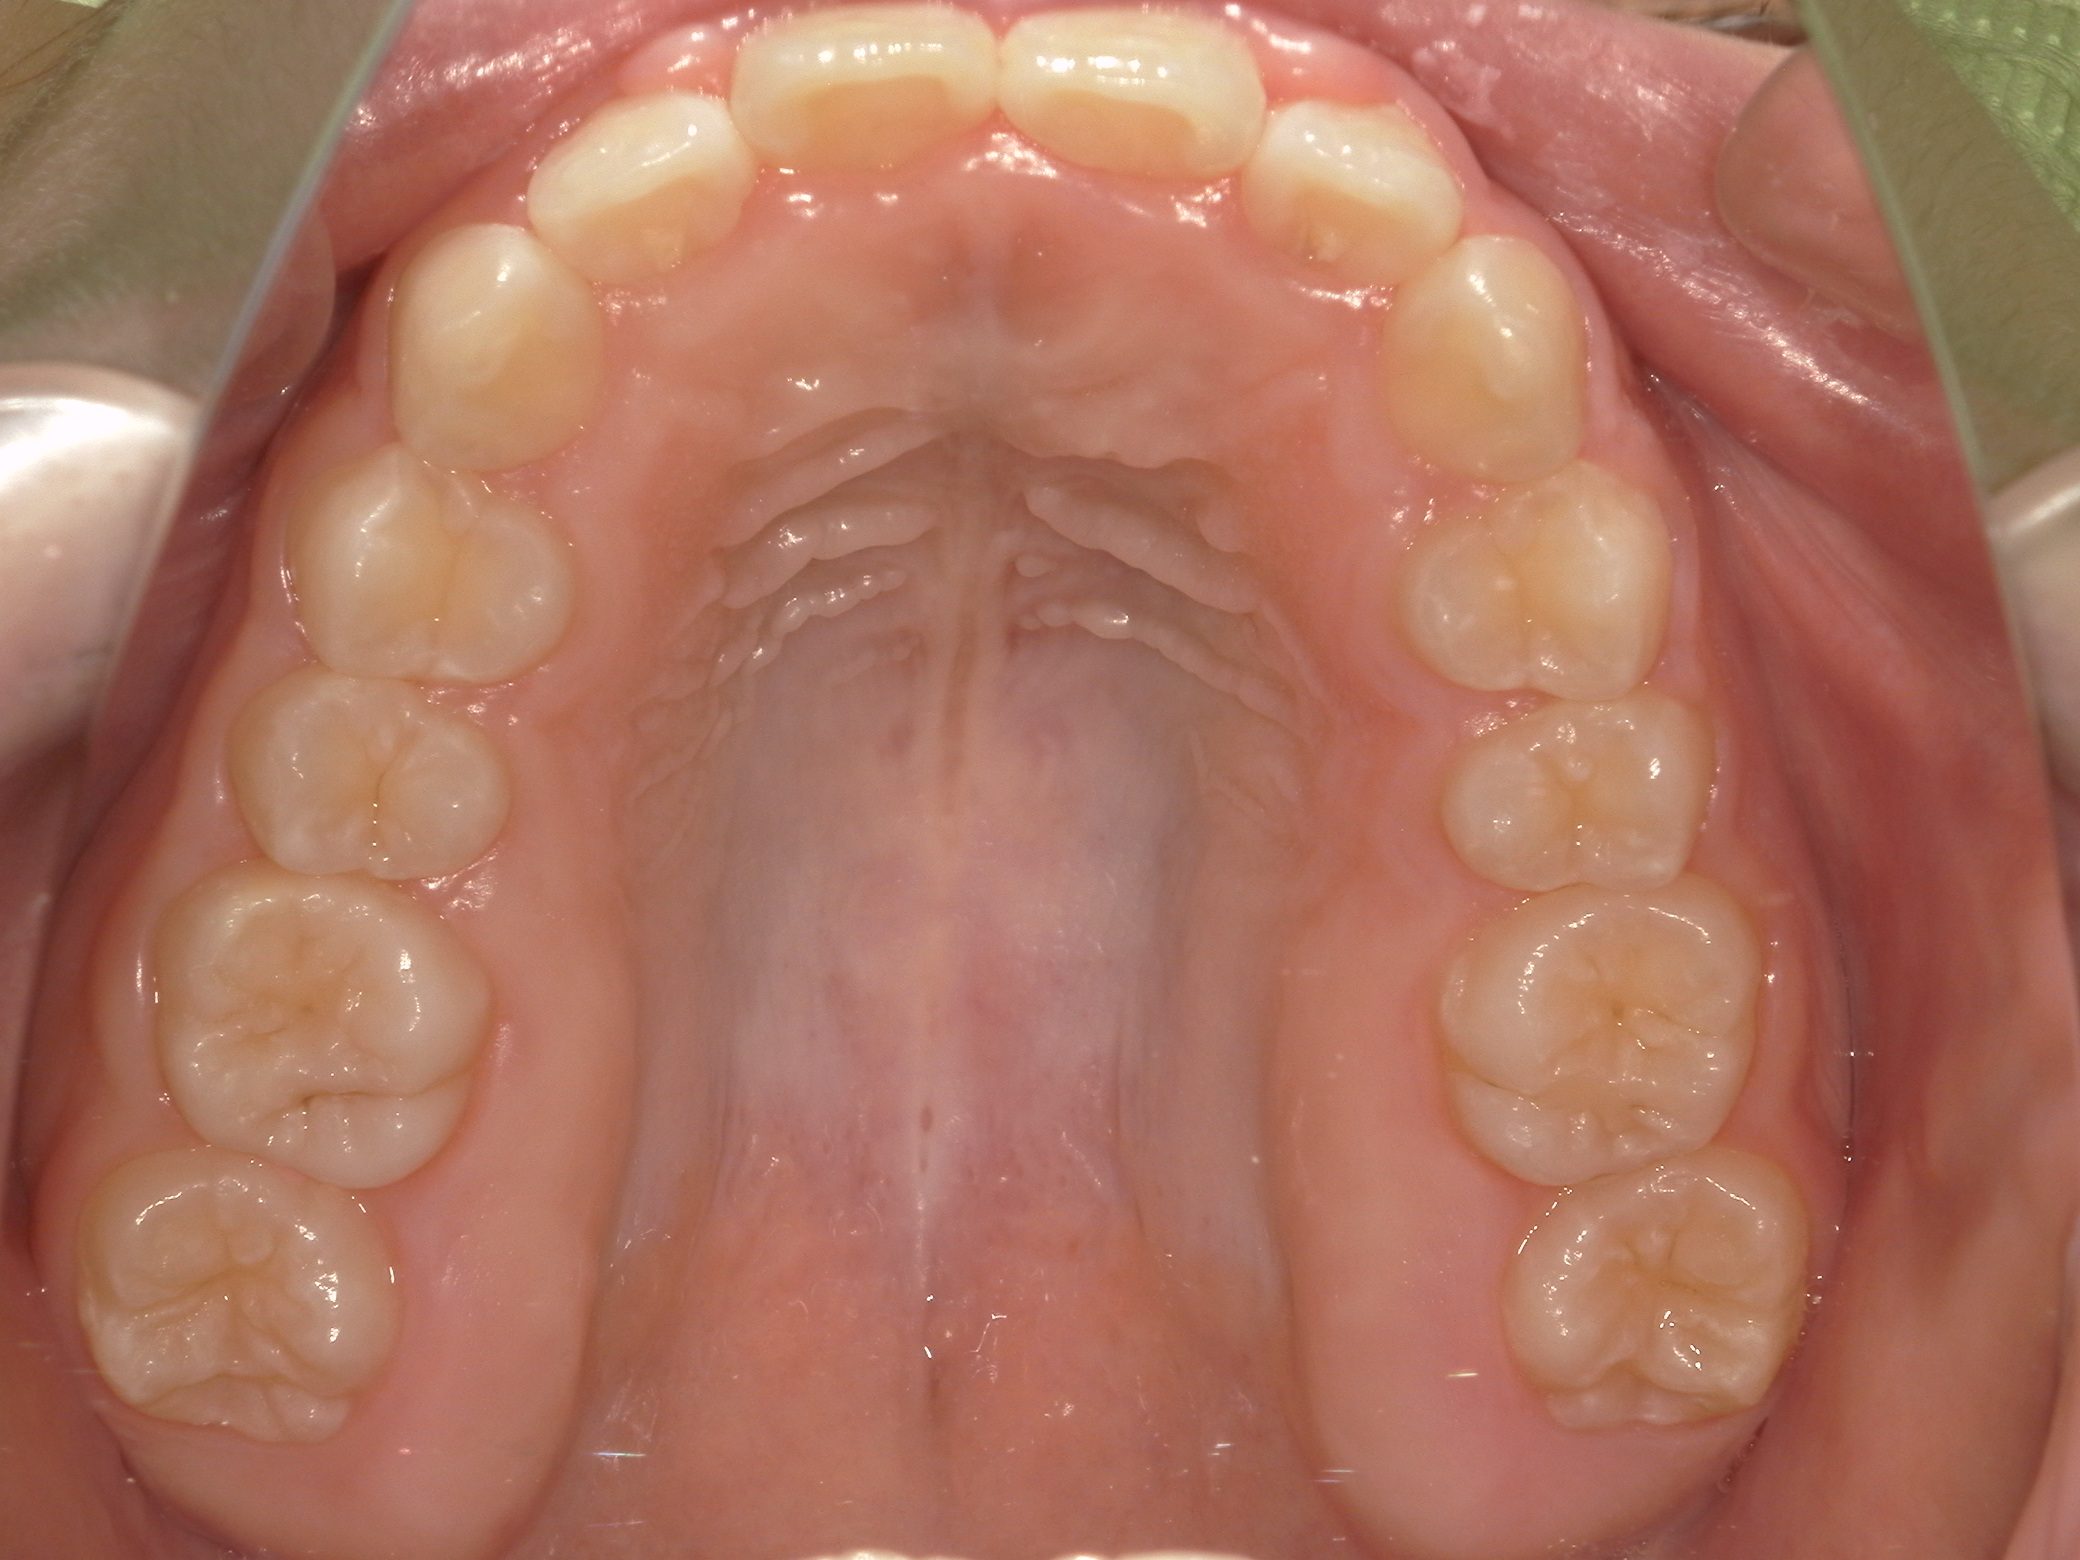

【中学生】インビザライン矯正 上顎前突(出っ歯)を改善

中学生以降

インビザライン フル

出っ歯

過蓋咬合

非抜歯

2期治療のみ

Before

After

治療期間

1.7年

治療開始

14歳歳

種類

インビザライン矯正

使用装置

インビザラインフル ディスキング併用

コメント

しっかり装着してくれて 予定通りに治療が終了しました。